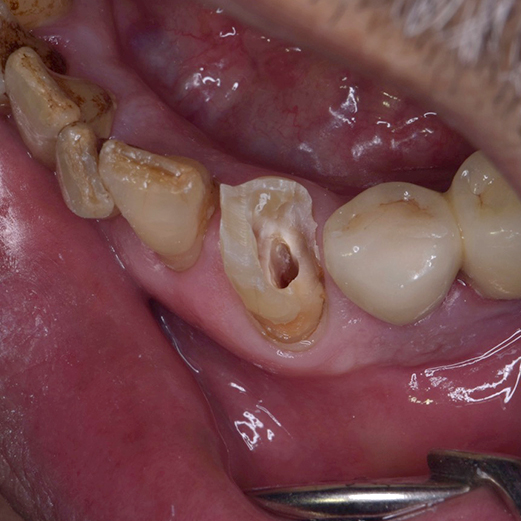

根管治療(歯の根っこの治療)は、虫歯が神経まで到達してしまった場合に、神経の通る管(根管)の組織を取り除いて、根っこをキレイにする治療の事です。歯根治療とも呼ばれます。

虫歯がひどくなると、歯の内部に細菌が侵入して神経にダメージを与えます。病気が進行すると神経は壊死し、根の先に病変を作ります。その際に根管治療が必要になります。

根管治療では、痛んだ歯髄を除去して、根管を注意深く清掃し、 再度の感染を防ぐために根の中に詰め物をします。